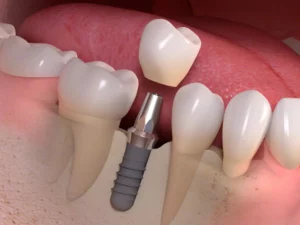

An implant is a titanium post that’s placed under your gum into the jaw bone. Your body grows bone over the implant keeping it well anchored. A new tooth is then designed to connect to the top of the implant so you can eat, speak and smile with confidence.

A dental implant is a small titanium post placed into the jawbone where a tooth is missing. Over time, the bone naturally fuses with the implant, creating a strong foundation. A custom-made crown, bridge, or denture is then attached to restore your smile.